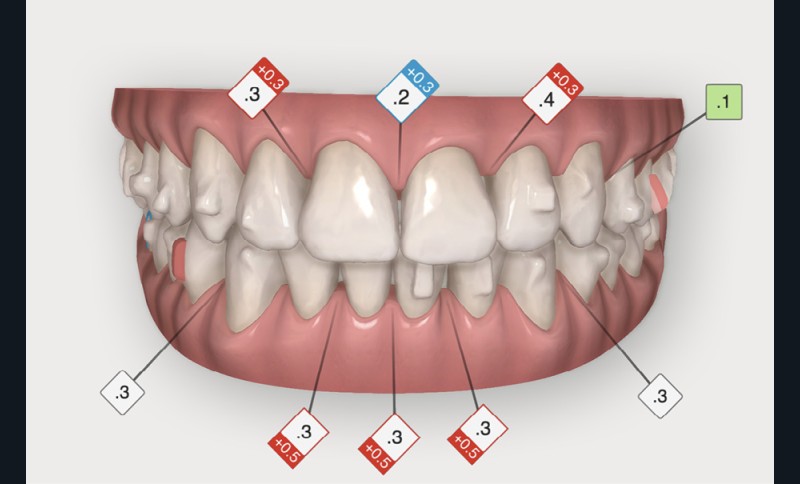

Après avoir traité les troubles transversaux et antéro-postérieurs, l’action orthodontique s’est concentrée sur les défauts d’alignement, grâce à des gouttières orthodontiques (fig. 4). L’avantage des gouttières par rapport aux dispositifs multi-attaches vestibulaires, c’est que l’alignement se fait avec une avancée moindre des bords libres des incisives et qu’elles permettent de définir plus précisément où l’on peut stripper pour gagner de la place et réduire les triangles noirs. En outre, le nettoyage des dents est facilité, ce qui est intéressant chez les patients ayant des atteintes parodontales.